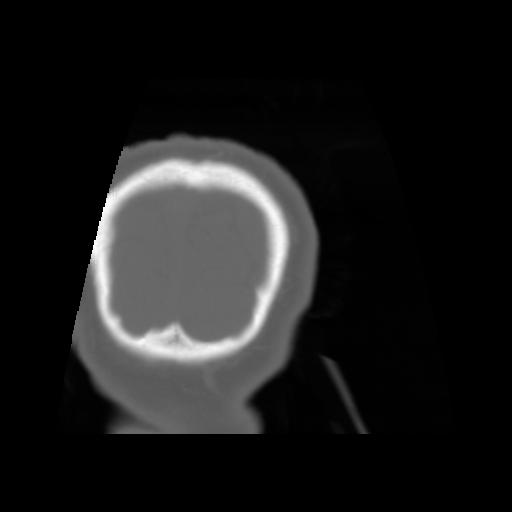

5 CEREBRO,,Coronal,3.000,CEREBRO,Coronal,